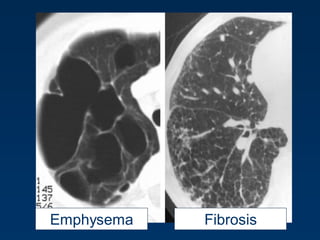

Emphysema

Emphysema typically presents as

areas of low attenuation without

visible walls as a result of

parenchymal destruction.

Permanent, abnormal enlargement of air

spaces distal to the terminal bronchiole

and accompanied by the destruction of

the walls of the involved air spaces.